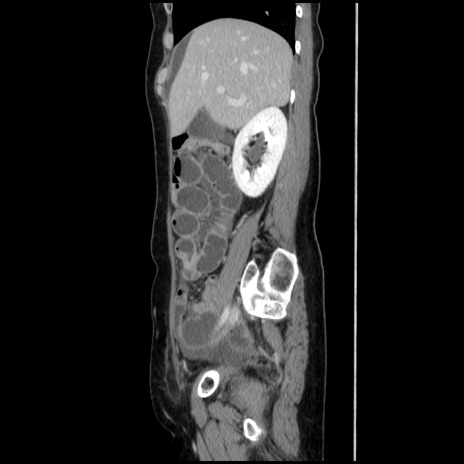

冠状断像

【症例】40歳代 女性

【主訴】上腹部痛、嘔気・嘔吐

【現病歴】約9時間前頃から急に上腹部痛、嘔気、嘔吐が出現。改善しないため救急要請。

【既往歴】子宮頚癌(広汎子宮全摘術、放射線療法)、腸閉塞

【身体所見】腹部:平坦、軟、腸雑音亢進、上腹部を中心に腹部全体に圧痛あり。

【データ】WBC 8400、CRP 0.03